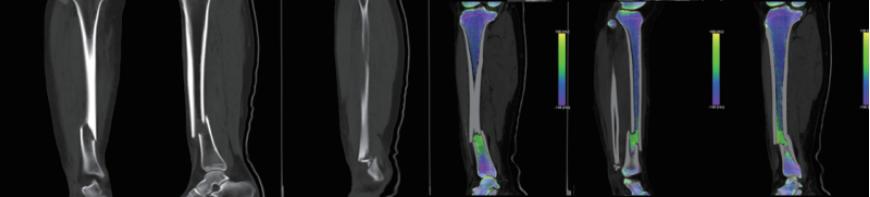

?雙能量成像技術(shù):具有定量及成分分析功能,可用于痛風石檢測,結(jié)石成分分析,骨髓顯像等;

案例圖

骨 髓 顯 像